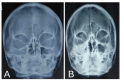

Figure 3

X-ray of paranasal sinuses before (A) and after (B) starting liposomal amphotericin B therapy